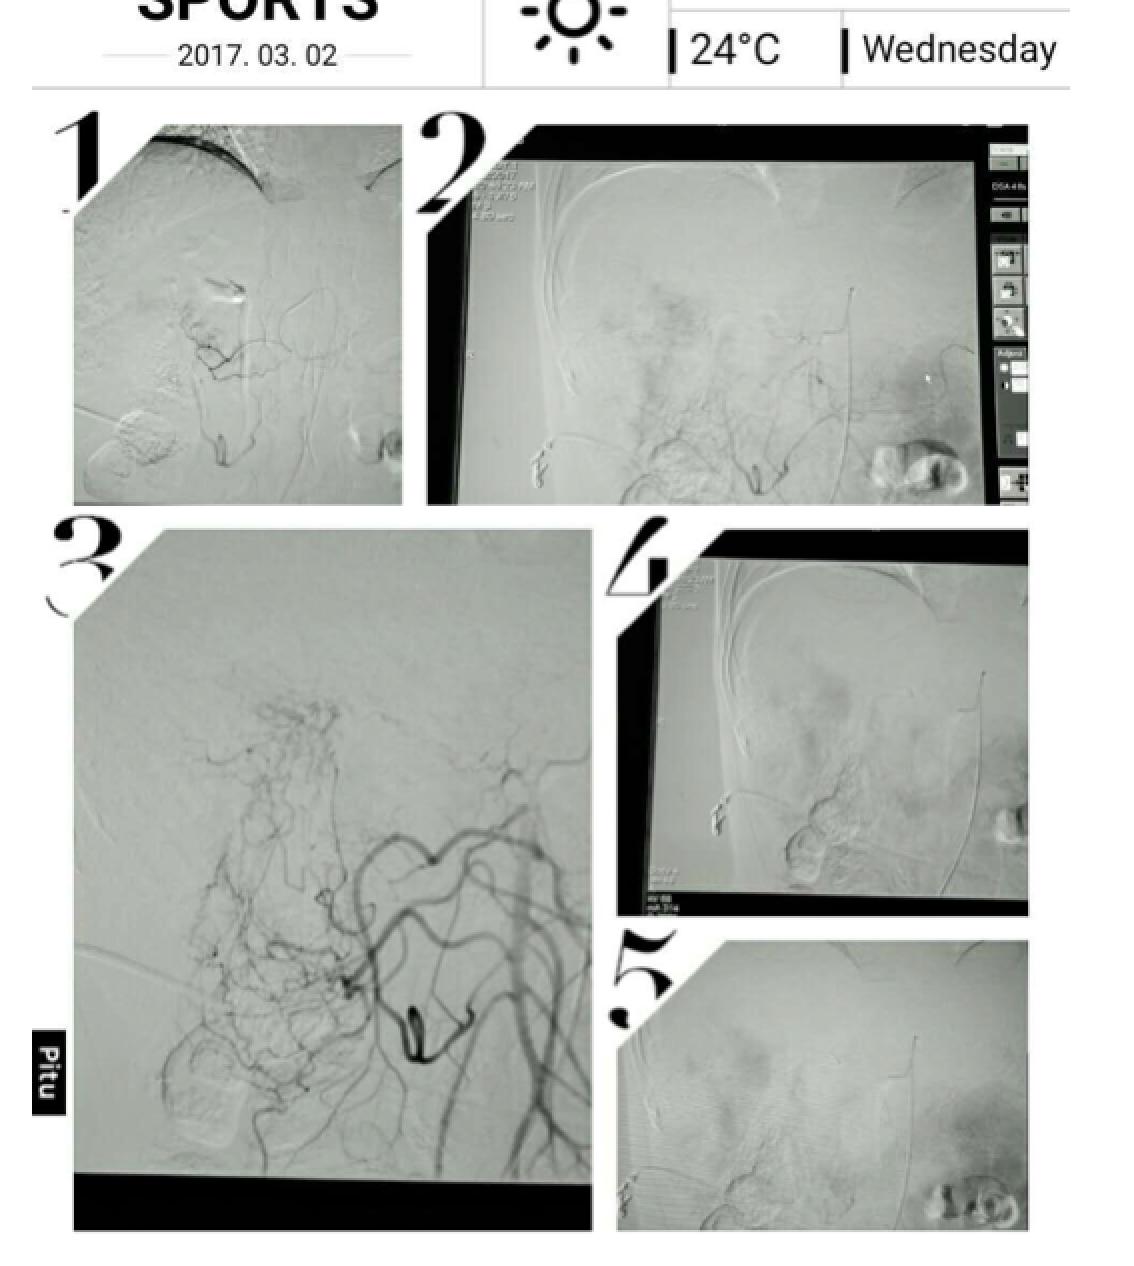

患者因纳差、烧心、腹痛、腹胀2月,于2016-01-17在某县人民医院行腹部CT示肝癌并门脉癌栓形成。分别于2016-01-22、2016-02-19于某市医院行两次TACE术(具体不详)。患者介入术后规律服用抗乙肝病毒、保肝、提高免疫力等药物治疗。2016-02-03至2016-04-30在某省立医院行5周期CIK免疫治疗。2016-05-18至2016-05-25于我院行射波刀治疗门静脉癌栓,具体放疗计划为:42Gy/7F。2016-06-24在我院行肝右动脉化疗栓塞术+肝右动脉灌注化疗术+间接门脉灌注化疗术,术中化疗总量,吡柔比星2mg、顺铂12mg、氟尿嘧啶250mg。分别于2016-05-10、2016-05-27、2016-06-13、2016-07-01、2016-07-27、2016-08-22、2016-09-19、2016-10-07、2016-10-19、2016-11-18、2016-12-18、2017-02-18行12周期免疫治疗。自2016-05-12起患者间断口服靶向药物阿帕替尼250-500mg/d,血压维持在220-130/95-70mmHg,血压升高期间伴上腹部不适,左侧为著,并向腰背部放射,偶尔反酸、烧心,剑突下疼痛,口服抑酸剂或进食后缓解,临床诊断为十二指肠溃疡,目前口服奥美拉唑、马来酸依那普利、氢氯噻嗪等药物对症降压。2017-03-02于我院行第二次肝右动脉化疗栓塞术+肝右动脉灌注化疗术+间接门脉造影术+肠系膜上动脉灌注化疗术。术中化疗总量,洛铂10mg、氟尿嘧啶500mg、吉西他滨400mg。目前间或皮下注射胸腺法新、重组人干扰素α-2b提高免疫力及慢性乙型病毒性肝炎治疗效果。

患者相关影像资料

4. 2017-3-15 DSA造影图中显示肿瘤组织血供一般,也未见癌栓显影,说明肿瘤组织或癌栓血供一般,也可能是靶向药物+栓塞化疗后,主要供血血管已闭塞,继续栓塞治疗效果有限。